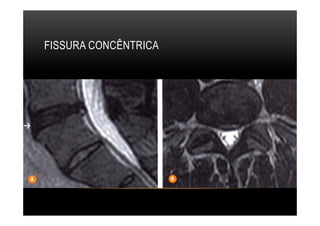

FISSURAS ANULARES

•  Concênctrica, são lesoes circunferenciais,nas camadas mais externas do anel

fibroso.

FISSURA CONCÊNTRICA